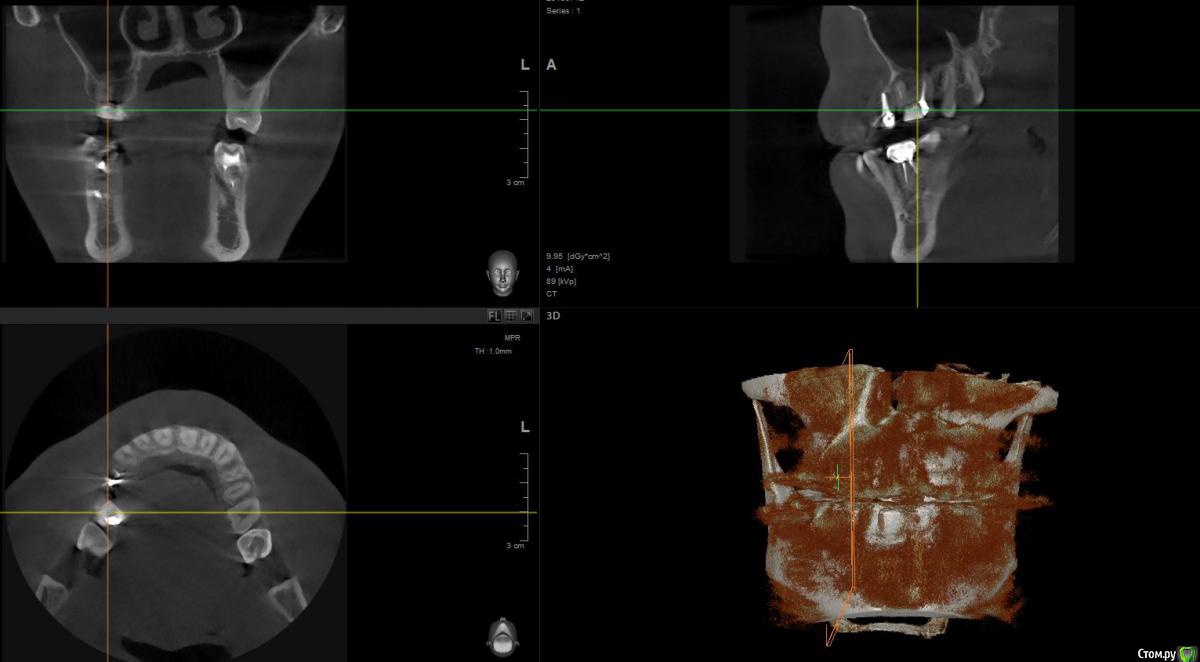

1 год назад были установлены 3 коронки. см Фото. После появления свища над верхней коронкой обратился к стоматологам.На фото 2 верхние коронки уже спилены и начато повторно лечение одного зуба,за мой счет конечно.

По результатам снимков след.вывод. Две верхние коронки снимать и лечить каналы , так там воспаление. Под нижней коронкой небольшое воспаление,но сказали пока его не трогать ,но взять под наблюдение.

post-48565-0-42560900-1469537779_thumb.jpg